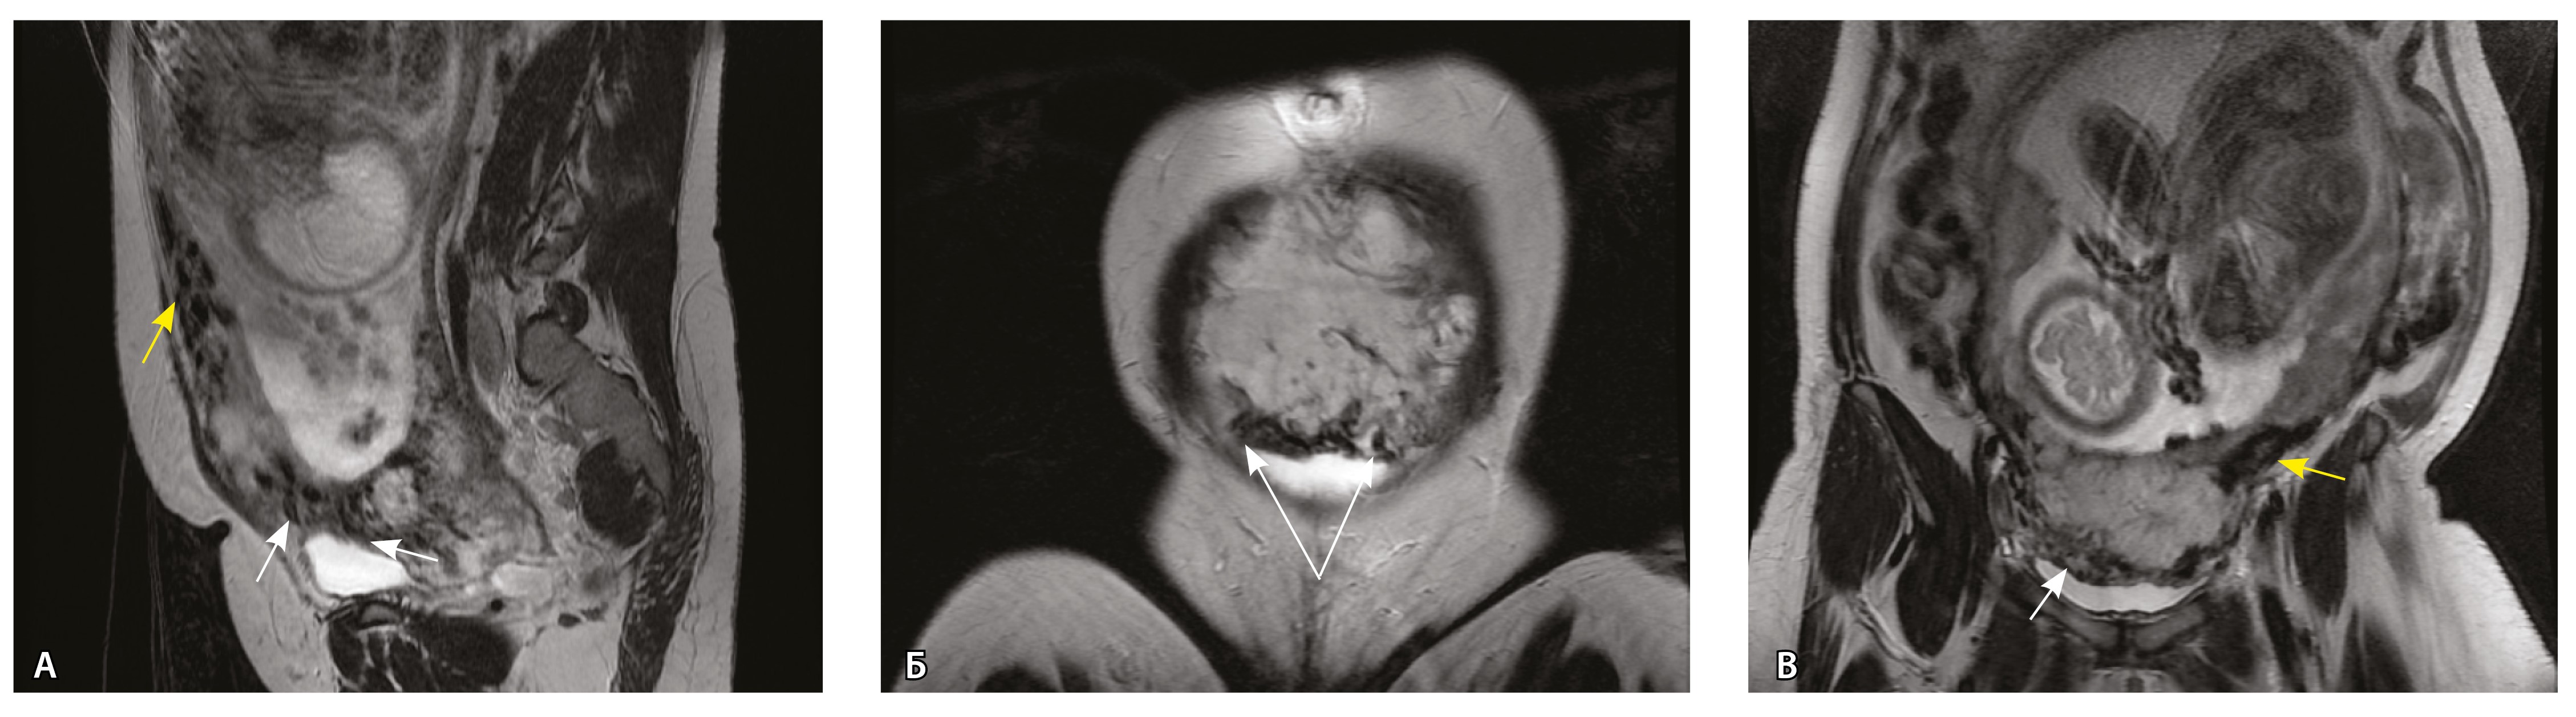

Сосуды 3-го типа. Внутриматочная гиперваскуляризация с дефицитом толщины миометрия, преимущественно сосуды срединного слоя, аналог pl. increta PAS 2, гестационная перестройка радиальных артерий (рис. 7).

Рис. 7. Беременность 34 недели, pl. increta, PAS 2 по FIGO. На магнитно-резонансных томограммах в режиме Т2-взвешенного изображения в сагиттальной (A, Б) и фронтальной (В) плоскостях определяется внутриматочная гиперваскуляризация с наличием многочисленных сливающихся сосудов в толще стенки матки, в области плацентарной площадки (белые стрелки); в нижнем маточном сегменте – выраженное истончение стенки матки, рубца от кесарева сечения с формированием маточной грыжи (желтые стрелки)

При pl. increta наличие патологических сосудов на изображениях МРТ связано с неполной гестационной перестройкой радиальных артерий, расположенных в срединном слое миометрия. Так, при окраске по Маллори они определяются как сжатые комплексы артерий среднего калибра, с частичным замещением внутренних слоев стенки матки, темно-красными фрагментами плодного фибриноида. На серийных срезах видно, что в этой артерии присутствует достаточное количество инвазивного цитотрофобласта (маркер цитокератин 8), но предыдущий срез подтверждает замещение мышечной оболочки фиброзной тканью как в стенке радиальной артерии, так и в периартериальном пространстве (рис. 8).

Сосуды 4-го типа. Наличие крупных извитых анастомозирующих сосудов, преимущественно по поверхности матки (в составе серозной оболочки матки) в сочетании с выраженным истончением нижнего сегмента матки (рис. 10).

Рис. 10. Беременность 33 недели, pl. percreta, PAS 3a по FIGO. На магнитно-резонансных томограммах в режиме Т2-взвешенного изображения в сагиттальной (A) и фронтальной (Б, В) плоскостях определяется внутриматочная гиперваскуляризация (желтые стрелки) и гиперваскуляризация в области выраженно истонченного нижнего маточного сегмента, с наличием многочисленных анастомозирующих сосудов по поверхности матки (белые стрелки); стенка матки в данной области представлена ретроплацентарными сосудами

Главным отличием крупных сосудов в составе серозной оболочки является то, что морфологически они находятся в пределах стенки матки. Об этом свидетельствует наличие в операционном материале тонкого поверхностного слоя мезотелия, отделяющего матку от брюшной полости (рис. 11). Его невозможно визуализировать методом МРТ из-за особенностей метода и толщины получаемых срезов.